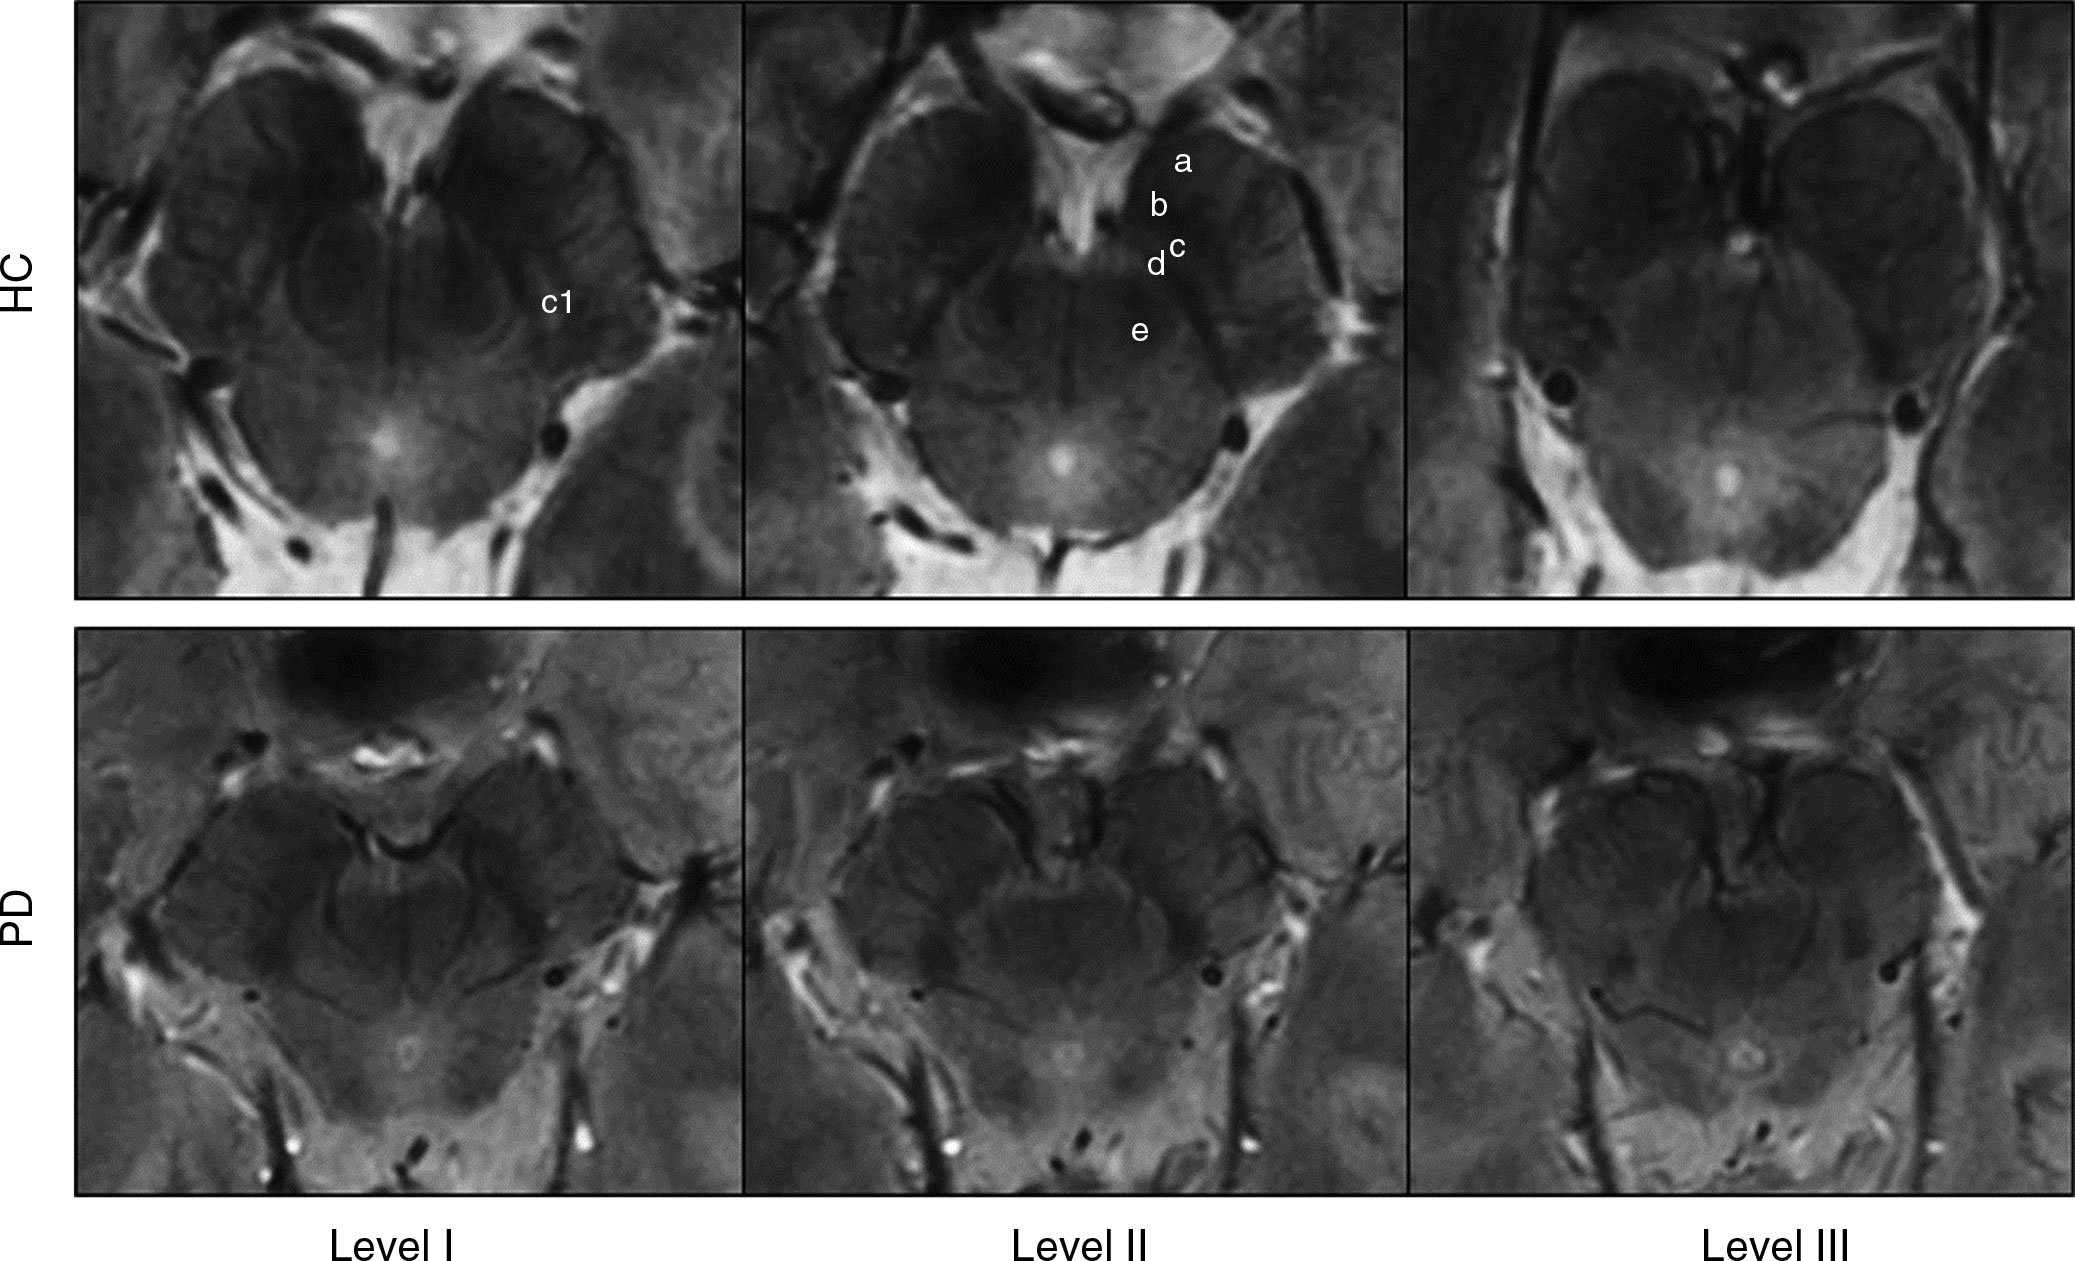

Using the 7-T MRI, the researchers were able to distinguish a three-layered organization of the substantia nigra (SN), a crescent-shaped mass of cells in the midbrain. Parkinson’s disease results from the loss of dopamine-producing cells located in this region of the brain.

Based on abnormalities in the SN identified by the 7-T MRI, the researchers correctly classified patients with Parkinson’s disease with a sensitivity of 100 percent and specificity of 96.2 percent.